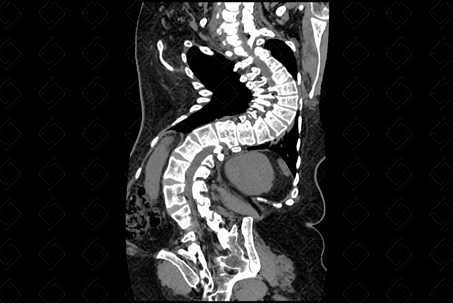

Descrição da figura: Tomografia computadorizada das colunas cervical, dorsal e lombar, plano coronal, evidenciando acentuada escoliose com convexidade para a esquerda.

• Tomografia computadorizada e ressonância magnética da coluna lombar são utilizadas, principalmente, nos casos não idiopáticos onde existem suspeitas de alterações congênitas, como hemivértebra, e para avaliação do canal medular. Muito ortopedistas também solicitam esses exames para adequado planejamento cirúrgico (figura acima).